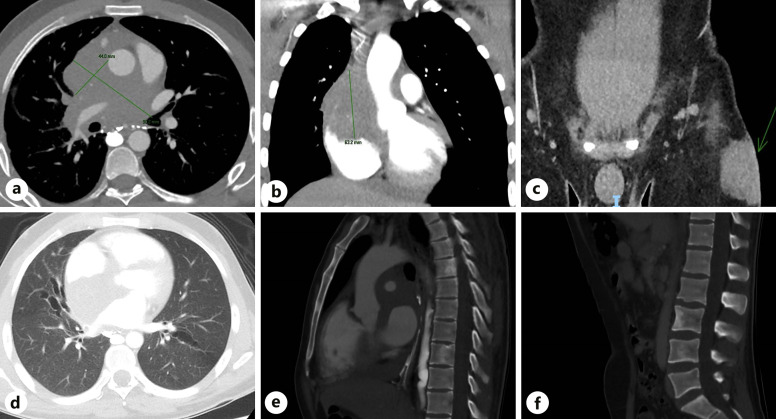

简介:黄曲霉菌是曲霉菌病的常见病因:黄曲霉菌是曲霉菌病的常见病因:病例介绍:一名居住在澳大利亚、身体健康、免疫功能正常的27岁男性发生了黄曲霉菌复合体播散性感染,并伴有纵隔和心脏受侵、上腔静脉阻塞和中风,并出现致命的出血性转变:结论:黄曲霉菌是导致免疫力低下者严重疾病的罕见但重要的病因。

Case presentation: A previously fit and well, immunocompetent 27-year-old male living in Australia developed disseminated A. flavus complex infection with mediastinal and cardiac invasion, superior vena cava obstruction and stroke, with fatal haemorrhagic transformation.